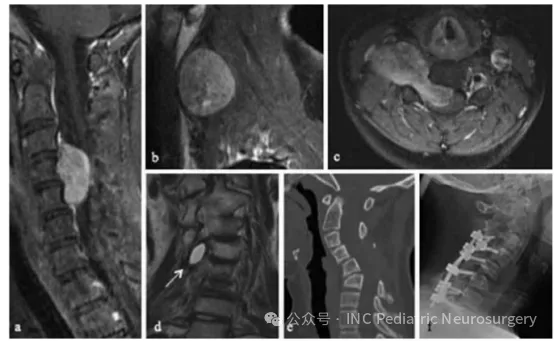

患者2

于2013年就诊,11岁,以颈部和手臂疼痛2周为主诉。MRI显示C1–C3大体积侵袭性脊索瘤,伴明显的右侧外向延伸(图2)。在外院患者接受C3–C5椎板切除术,但由于术中体感诱发电位(SSEP)信号丢失,肿瘤切除不完全且手术被迫中止。

转入SickKids儿童医院后,患者接受了右前外侧颈部入路的肿瘤切除,达到肿瘤全切(gross total resection)。病理为经典型,免疫组化结果S100、广谱细胞角蛋白(pan-CK)、CK-19、CK-8、癌胚抗原(CEA)、低分子量细胞角蛋白(LMW-K)、波形蛋白(vimentin)以及EMA均为阳性。

术后随访影像示少量右侧囊性残留,通过光子放疗70 Gy得到良好控制。手术及放疗两年后,患者出现颈椎后凸侧弯(cervical kyphoscoliosis)并伴颈部疼痛,随后接受C3–T1内固定融合术。

图2.患者2:C3–C5脊索瘤影像示例

(a)术前矢状位T1加权MRI(增强gadolinium);

(b)术前右侧旁矢状位T1加权增强MRI;

(c)术前水平位T1加权增强MRI;

(d)术后冠状位T2加权MRI,可见囊性残留(箭头);

(e)术后2年矢状位CT,可见进行性颈椎后凸侧弯(kyphoscoliosis);

(f)术后C3–T1内固定融合侧位X线片。